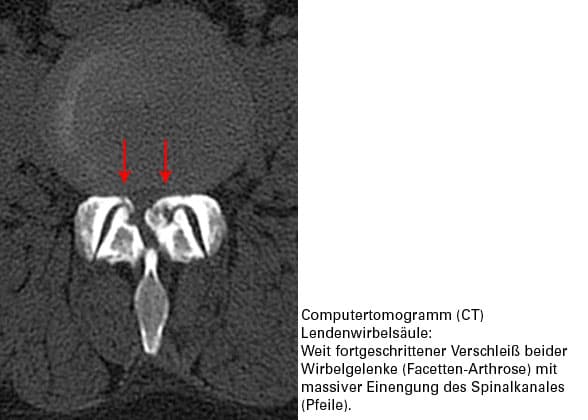

Das Schicksal der Wirbelgelenke wird von der BS entschieden

Wenn die Distanzscheibe zwischen 2 Wirbeln, also die Bandscheibe, dünner wird, treten die Wirbel näher aufeinander zu. Die Wirbelgelenke geraten unter einen erhöhten Druck. Gleichzeitig wird die betroffene Bandscheiben-Etage instabil. Das Scharnier Wirbelgelenk bekommt ein krankhaftes Bewegungsspiel, das Gelenk selbst wird instabil.

Instabilität des Wirbelgelenkes unter erhöhter Druckbelastung – diese Kombination löst Verschleißerscheinungen im Gelenk selbst aus. Wir sprechen von einer Wirbelgelenksarthrose (Facetten-Arthrose). Wenn die Bewegungen im Wirbelgelenk von der Muskulatur nicht präzise und stabil geführt werden, kommt es zu Fehlbelastungen im Gelenk. Dies verursacht Schmerzen. Diese werden meist stichartig empfunden. Die Wirbelsäule versucht sofort, den Schmerz "abzuschalten".